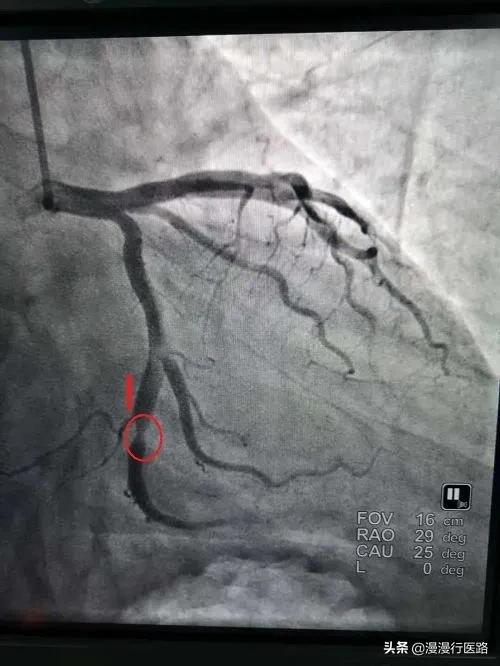

- Il existe trois artères coronaires principales dans le cœur, qui sont divisées en branche descendante antérieure, artère coronaire droite et branche circonflexe. Si un stent est placé dans l'un de ces vaisseaux en raison d'une sténose sévère, mais qu'il subsiste une sténose dans d'autres parties du corps, il se peut que le patient ne soit toujours pas apte à effectuer un travail physique.

3. en fonction de leurs propres conditions vasculaires, en fonction de leurs propres forces

Chez certaines personnes, il n'y a qu'une ou deux lésions dans le vaisseau sanguin, et après l'implantation du stent, le vaisseau sanguin est presque complètement normal, de sorte qu'elles peuvent pratiquer des activités physiques d'une intensité relativement élevée ; tandis que chez d'autres personnes, les lésions dans le vaisseau sanguin sont très diffuses, et le stent ne résout que le problème de la zone sévèrement sténosée, et il reste des lésions résiduelles, de sorte que les activités physiques à ce moment-là doivent être contrôlées à un niveau adéquat.